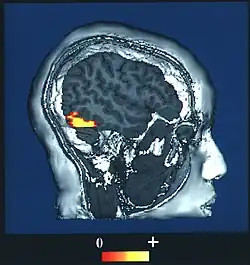

Dans le système nerveux central, la région de l'amygdale (zone sous-corticale) est connue pour être le lieu du conditionnement de la peur, et elle contribue à consolider des souvenirs émotionnels[16],[17]. L'amygdale joue un rôle majeur dans l'évaluation (subjective et presque immédiate) du degré de confiance qu'on peut donner à une personne (« fiabilité » du visage)[18],[19],[20].